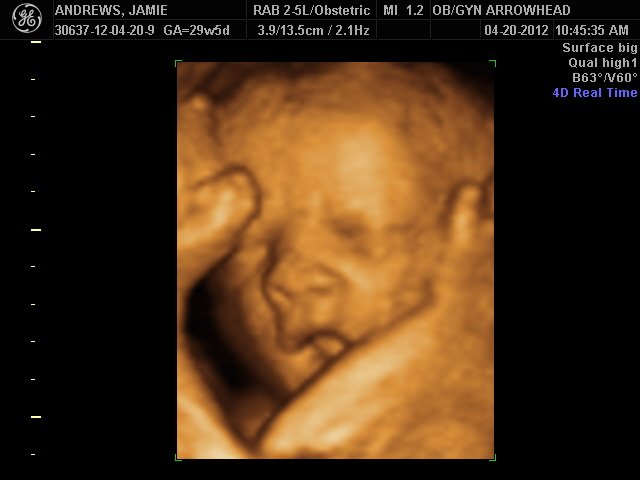

We offer complimentary 3D/4D Ultrasounds to all our OB patients around 30 weeks! The following photos are some examples of our work, shown with permission from our patients.